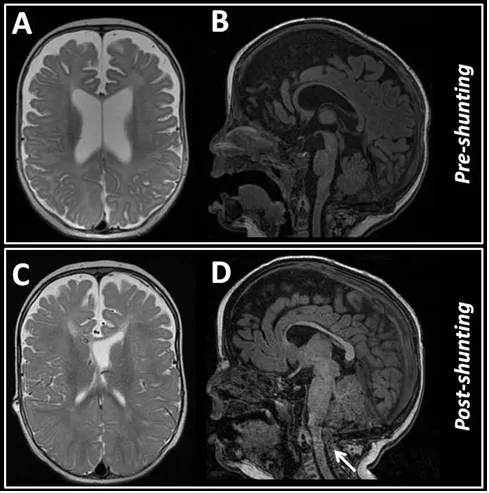

计算机断层扫描显示,患儿双侧鳞状缝和顶乳突缝过早融合,但颅顶骨缝呈开放状态。脑部磁共振成像显示中度脑室扩大,伴有扩大的脑周蛛网膜下腔间隙,以及后颅窝天幕低位附着,未见Chiari畸形或神经结构拥挤表现。血管磁共振序列显示静脉模式正常。通过脑实质内传感器进行的长时间颅内压监测显示病理性高值。因此,患儿首先接受了脑室腹腔分流管置入术,术前症状迅速得到缓解。术中获取的脑脊液样本检查未发现感染证据。

图2.初次就诊时进行的脑磁共振成像(MRI)显示脑室扩张,但无明显迹象表明脑脊液循环受阻(B、C)。两个月后进行的MRI检查排除了分流器功能异常的情况,但显示后颅窝空间拥挤,伴有Chiari型畸形(C、D),箭头所示。